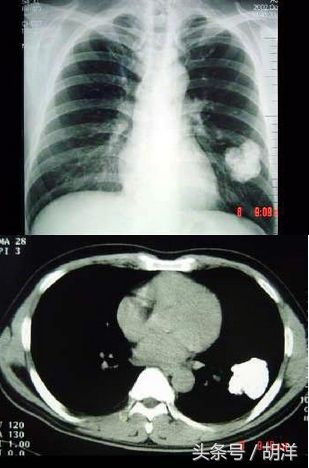

钙化灶常能排除恶性肿瘤可能

肺部的病灶如果其中有钙质,特别是钙质出于病灶的中间部位或者占病灶体积的绝大多数,则恶性的可能性比较小,如果钙化部位出于病灶的边缘或者偏于一侧,则并不能完全排除肿瘤的可能性。